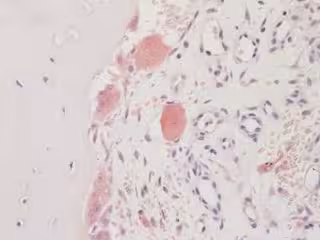

Las nuevas células, que los investigadores denominan osteomorfos, se encuentran en la sangre y la médula ósea y se fusionan para formar osteoclastos, células especializadas que descomponen el tejido óseo. Tienen un perfil genómico único que revela objetivos terapéuticos prometedores y aún inexplorados.

Para comprender mejor la resorción ósea y cómo tratarla, los investigadores del Garvan investigaron los osteoclastos, las células especializadas en la reabsorción ósea, en un modelo experimental. Usando tecnología de imágenes intravitales que permite una mirada profunda dentro del tejido óseo vivo, los investigadores notaron que los osteoclastos hicieron algo inusual: se dividieron en células más pequeñas y luego se unieron nuevamente para formar osteoclastos nuevamente.